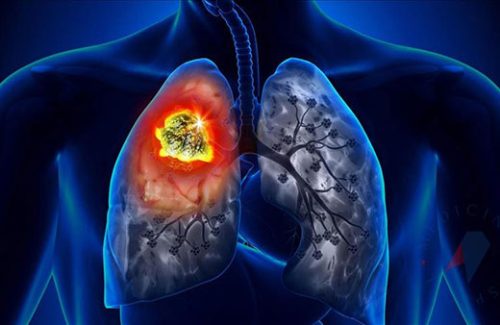

Akciğer kanseri, akciğerlerde kontrolsüz hücre büyümesi sonucu oluşan bir tür kanserdir. Genellikle sigara içmek gibi risk faktörleri ile ilişkilidir, ancak sigara içmeyenlerde de görülebilir. Erken teşhis edilmediğinde, akciğer kanseri ilerleyebilir ve tedavi edilmesi zor olabilir. Bu nedenle, belirtileri tanımak ve risk faktörlerini azaltmak önemlidir.

Akciğer kanseri teşhisi genellikle görüntüleme testleri (örneğin, bilgisayarlı tomografi veya BT taraması) ve biyopsi ile konulur. Tedavi seçenekleri tümörün tipine, evresine ve hastanın genel sağlık durumuna bağlı olarak değişir. Tedavi seçenekleri arasında cerrahi müdahale, kemoterapi, radyoterapi ve hedefe yönelik ilaç tedavisi bulunmaktadır. Erken teşhis, tedavi seçeneklerini ve hastalıkla başa çıkma şansını artırabilir.